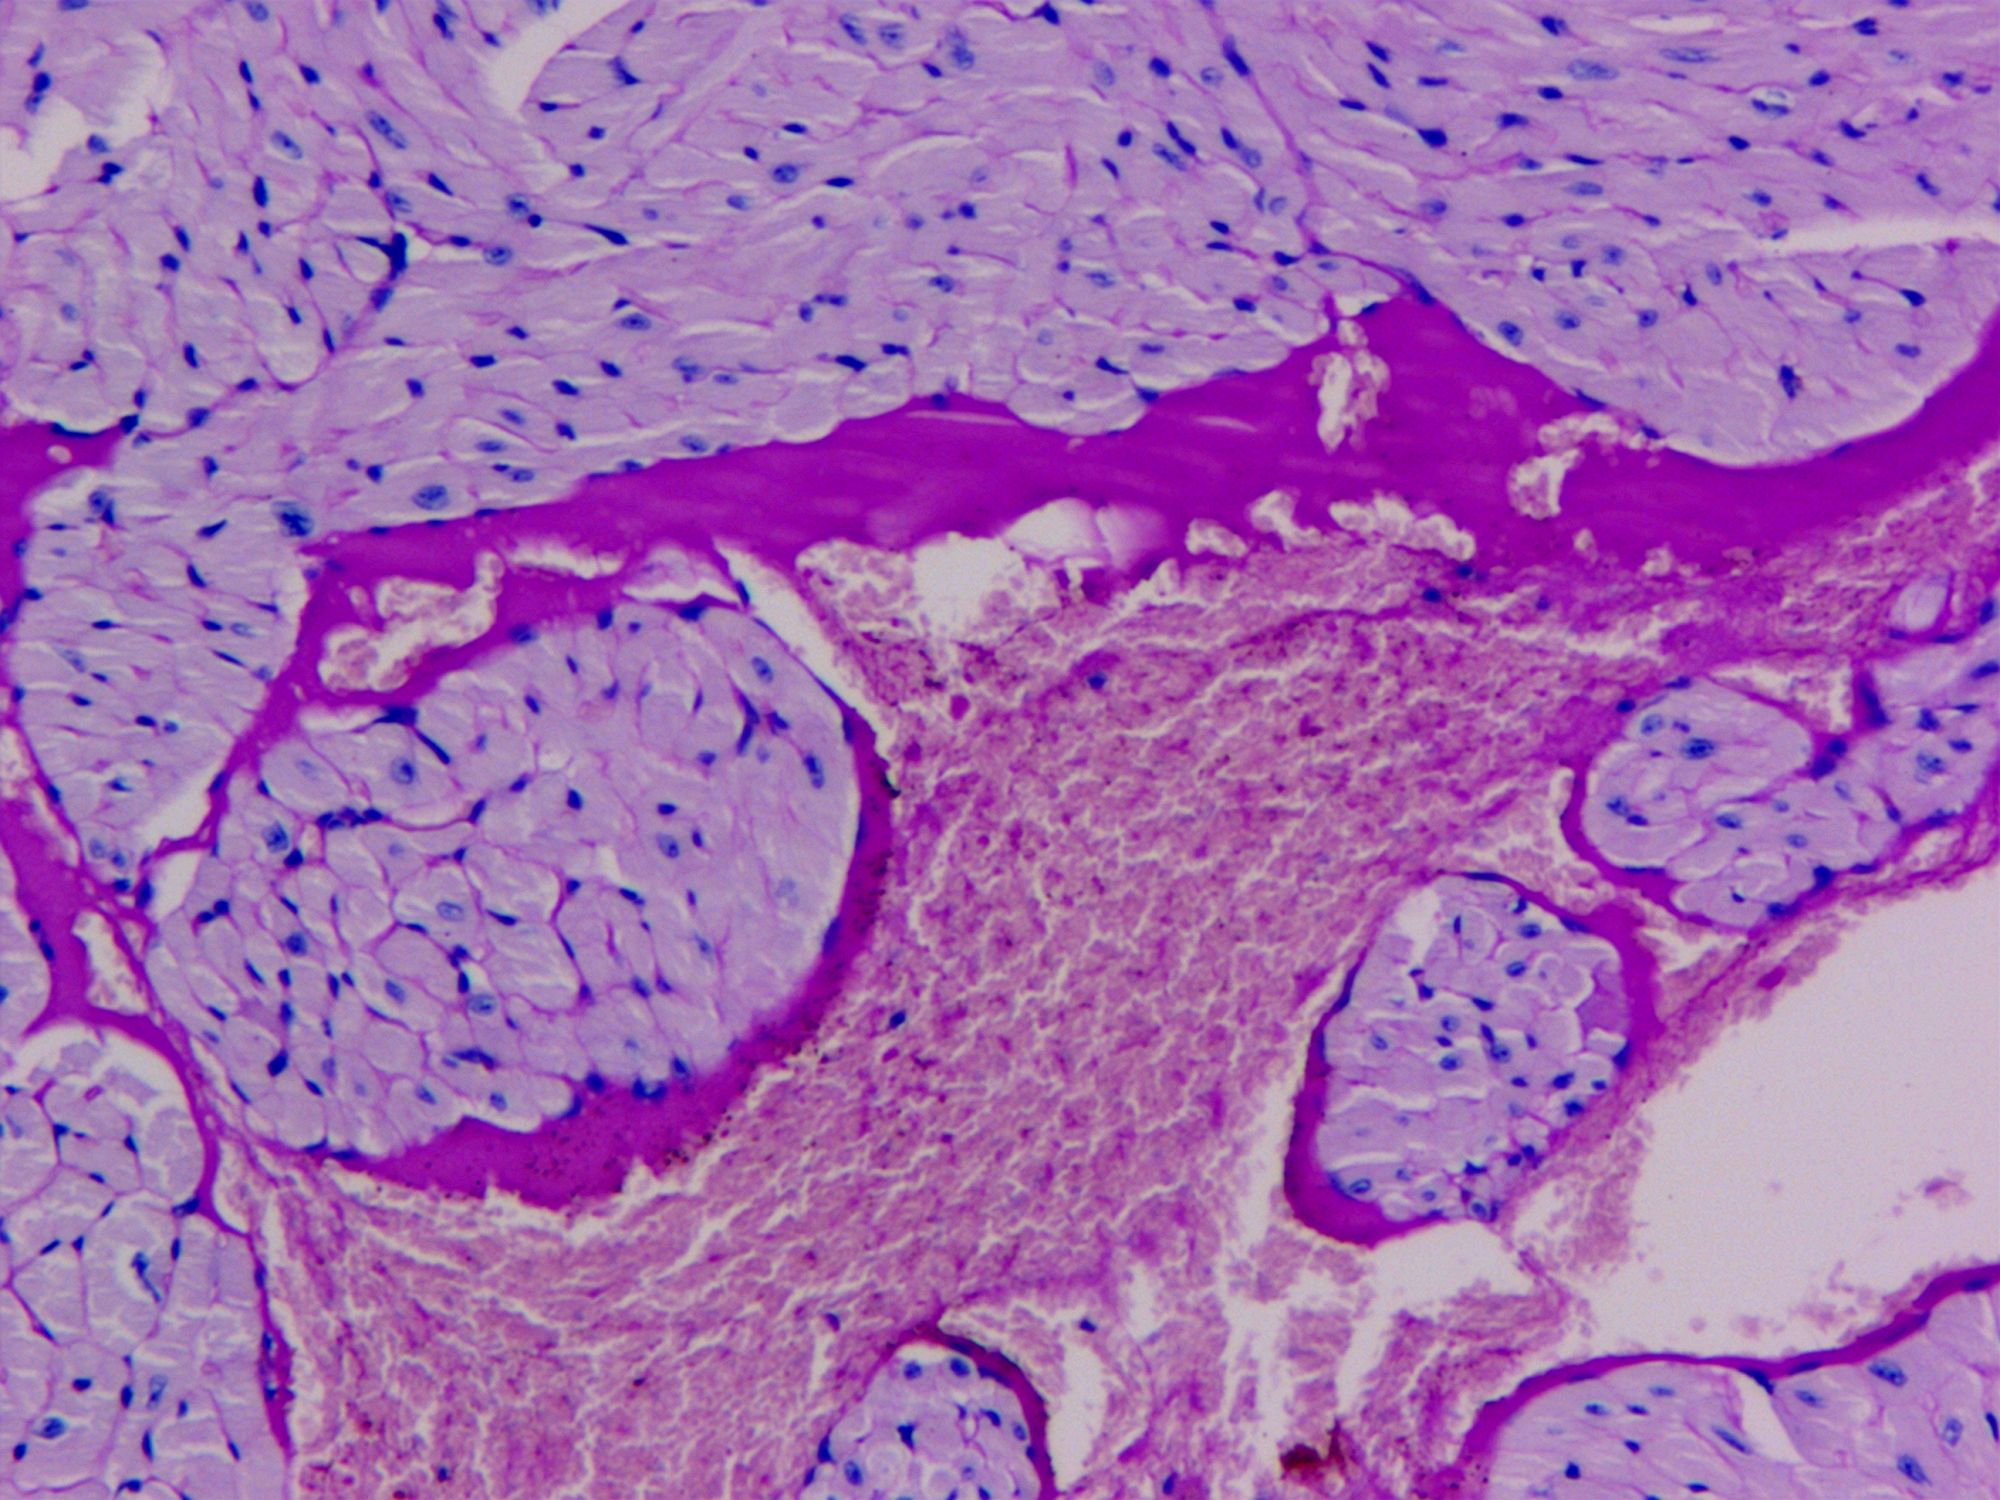

PAS糖原染色

PAS染色法(Periodic Acid-Schiff stain)在組織學(xué)上,又稱過碘酸雪夫染色,糖原染色。一般用來顯示糖元和其它多糖物質(zhì),過碘酸把糖類相鄰兩個(gè)碳上的羥基氧化成醛基,再用Schiff試劑和醛基反應(yīng)使呈現(xiàn)紫紅色。

PAS染色糖原染色是病理學(xué)中常規(guī)的染色方法之一,氧化劑能氧化糖類及有關(guān)物質(zhì)中的1,2-乙二醇基,使之變?yōu)槎?,醛與Schiff試劑能結(jié)合成一種品紅化合物,產(chǎn)生紫紅色。PAS技術(shù)常用來顯示糖原和其他多糖,該染色液不僅能夠顯示糖原,還能顯示中性黏液性物質(zhì)和某些酸性物質(zhì),以及軟骨、垂體、霉菌、真菌、色素、淀粉樣物質(zhì)、基底膜等。

PAS反應(yīng)陽性物質(zhì) 紅色或紫紅色

細(xì)胞核 藍(lán)色

細(xì)胞質(zhì) 深淺不一的紅色